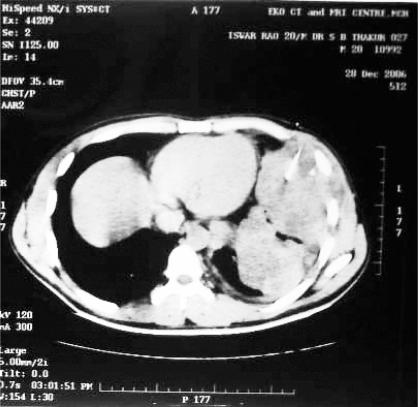

We present a case report of a 20 years old male who had low grade fever, weight loss of about 10 kg and left-sided chest pain increasing in intensity over a year. Clinically, it mimicked left sided pleural effusion with a tender, soft, parietal swelling in left in-fraaxillary area. Chest x-ray and Computerized Tomography-scan of thorax showed pleura based mass in left hemi thorax. Computerized Tomography guided Fine Needle Aspiration Cytology confirmed the diagnosis of non Hodgkin Lymphoma, diffuse large B cell type, high-grade.

我们报告一例20岁男性病例,该患者持续低热,体重减轻约10公斤,左侧胸痛,疼痛强度在一年中逐渐增加。临床上,其表现类似左侧胸腔积液,左侧腋下部有一个压痛、柔软的胸壁肿物。胸部X光和胸部计算机断层扫描显示左半胸有一个胸膜肿物。计算机断层扫描引导下细针穿刺细胞学检查确诊为非霍奇金淋巴瘤,弥漫大B细胞型,高级别。